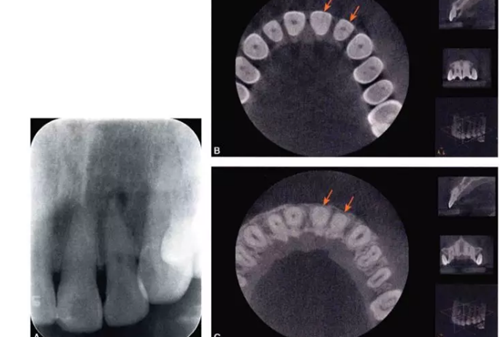

完全鈣化根管在X線片上的表現(xiàn)是根管影像模糊,密度增高,根管密度與周圍的牙本質(zhì)密度接近,甚至無法區(qū)分根管與牙本質(zhì)的影像。有些根管,可表現(xiàn)為根管影像時斷時續(xù)或模糊不清,為不完全鈣化根管表現(xiàn)(圖4-1A)。細(xì)小根管的病例在X線片上,根管影像隱約可見,與同名牙或鄰牙相比,根管較為細(xì)小影像清晰度降低。

目前,小視野CBCT物理層厚可達(dá)76m,對根管系統(tǒng)的顯示明顯優(yōu)于其他影像學(xué)手段。觀察根管的CBCT圖像,冠根向橫斷面能夠比較直觀地顯示根管中央的鈣化情況。觀察時可從髓底開始,將橫截面斷層由冠方向根尖方向推移,逐層觀察。正常根管位于牙根的中央部位,呈圓形或橢圓形暗影,與周圍的牙本質(zhì)所顯示的致密白色影像有明顯區(qū)別。細(xì)小鈣化根管表現(xiàn)為橫截面中央的暗影變淡、消失,與周圍牙本質(zhì)影密度接近或相同,與同一患牙其他根管及正常鄰牙的根管影像則有明顯區(qū)別。通過CBCT,還可以測量鈣化根管的長度及范圍(圖4-1B、C)。